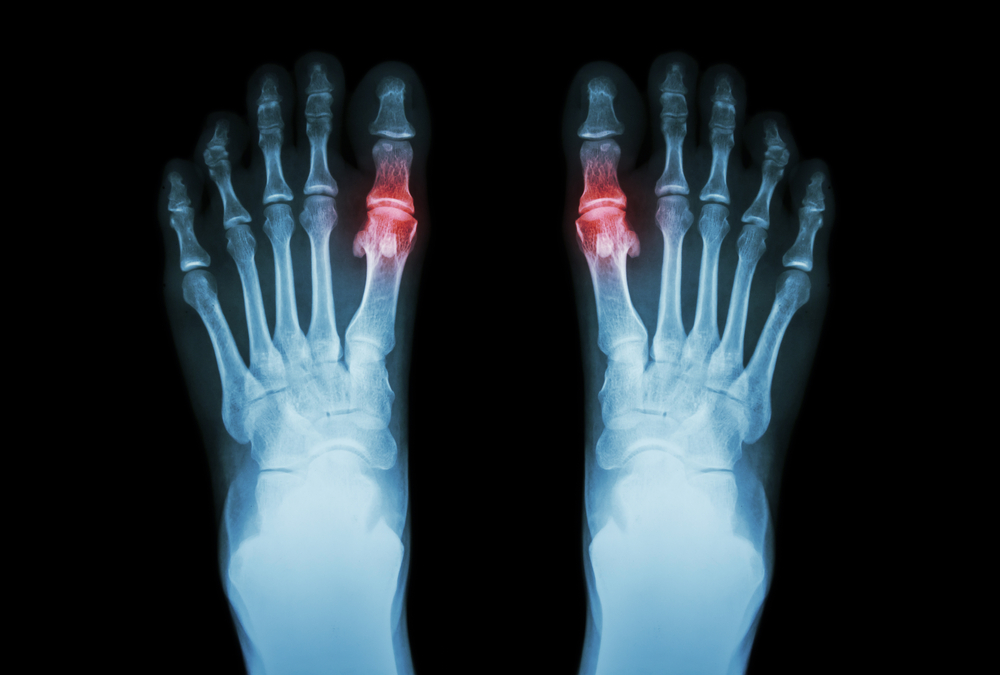

Ask a Foot Specialist: Will I Need Surgery for a Metatarsal Injury?

by jbaker@support.websitepro.hosting | Oct 15, 2021 | Blog

Your metatarsals are the bones in your toes that connect to the rest of the foot. There are five in each foot, and all are long and thin, with a knob-like structure at the end where they connect to the toe bones. Sometimes, especially when you’re being active,...